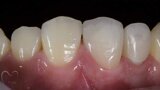

Esthetic Rehabilitation of Maxillary Anterior Teeth: Dr Sanjay Sah